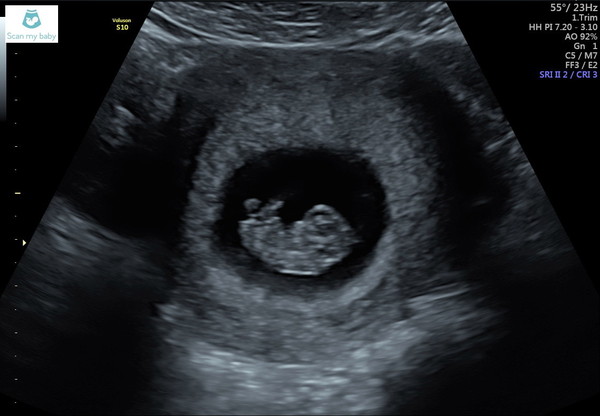

This is baby Avocuddles.... 9 weeks today and measuring 22mm - the size of a big grape! Really hoping my 12 week scan date comes through soon. @SunStruck where I live the appointment just comes through the post, I'm hoping it's no later than 12 weeks as still feeling nervous though obviously happier after today's positive scan. My DH is still feeling too cautious to get at all excited, I think if things look good at 12 weeks we both finally might be able to accept that we might bring a baby home....